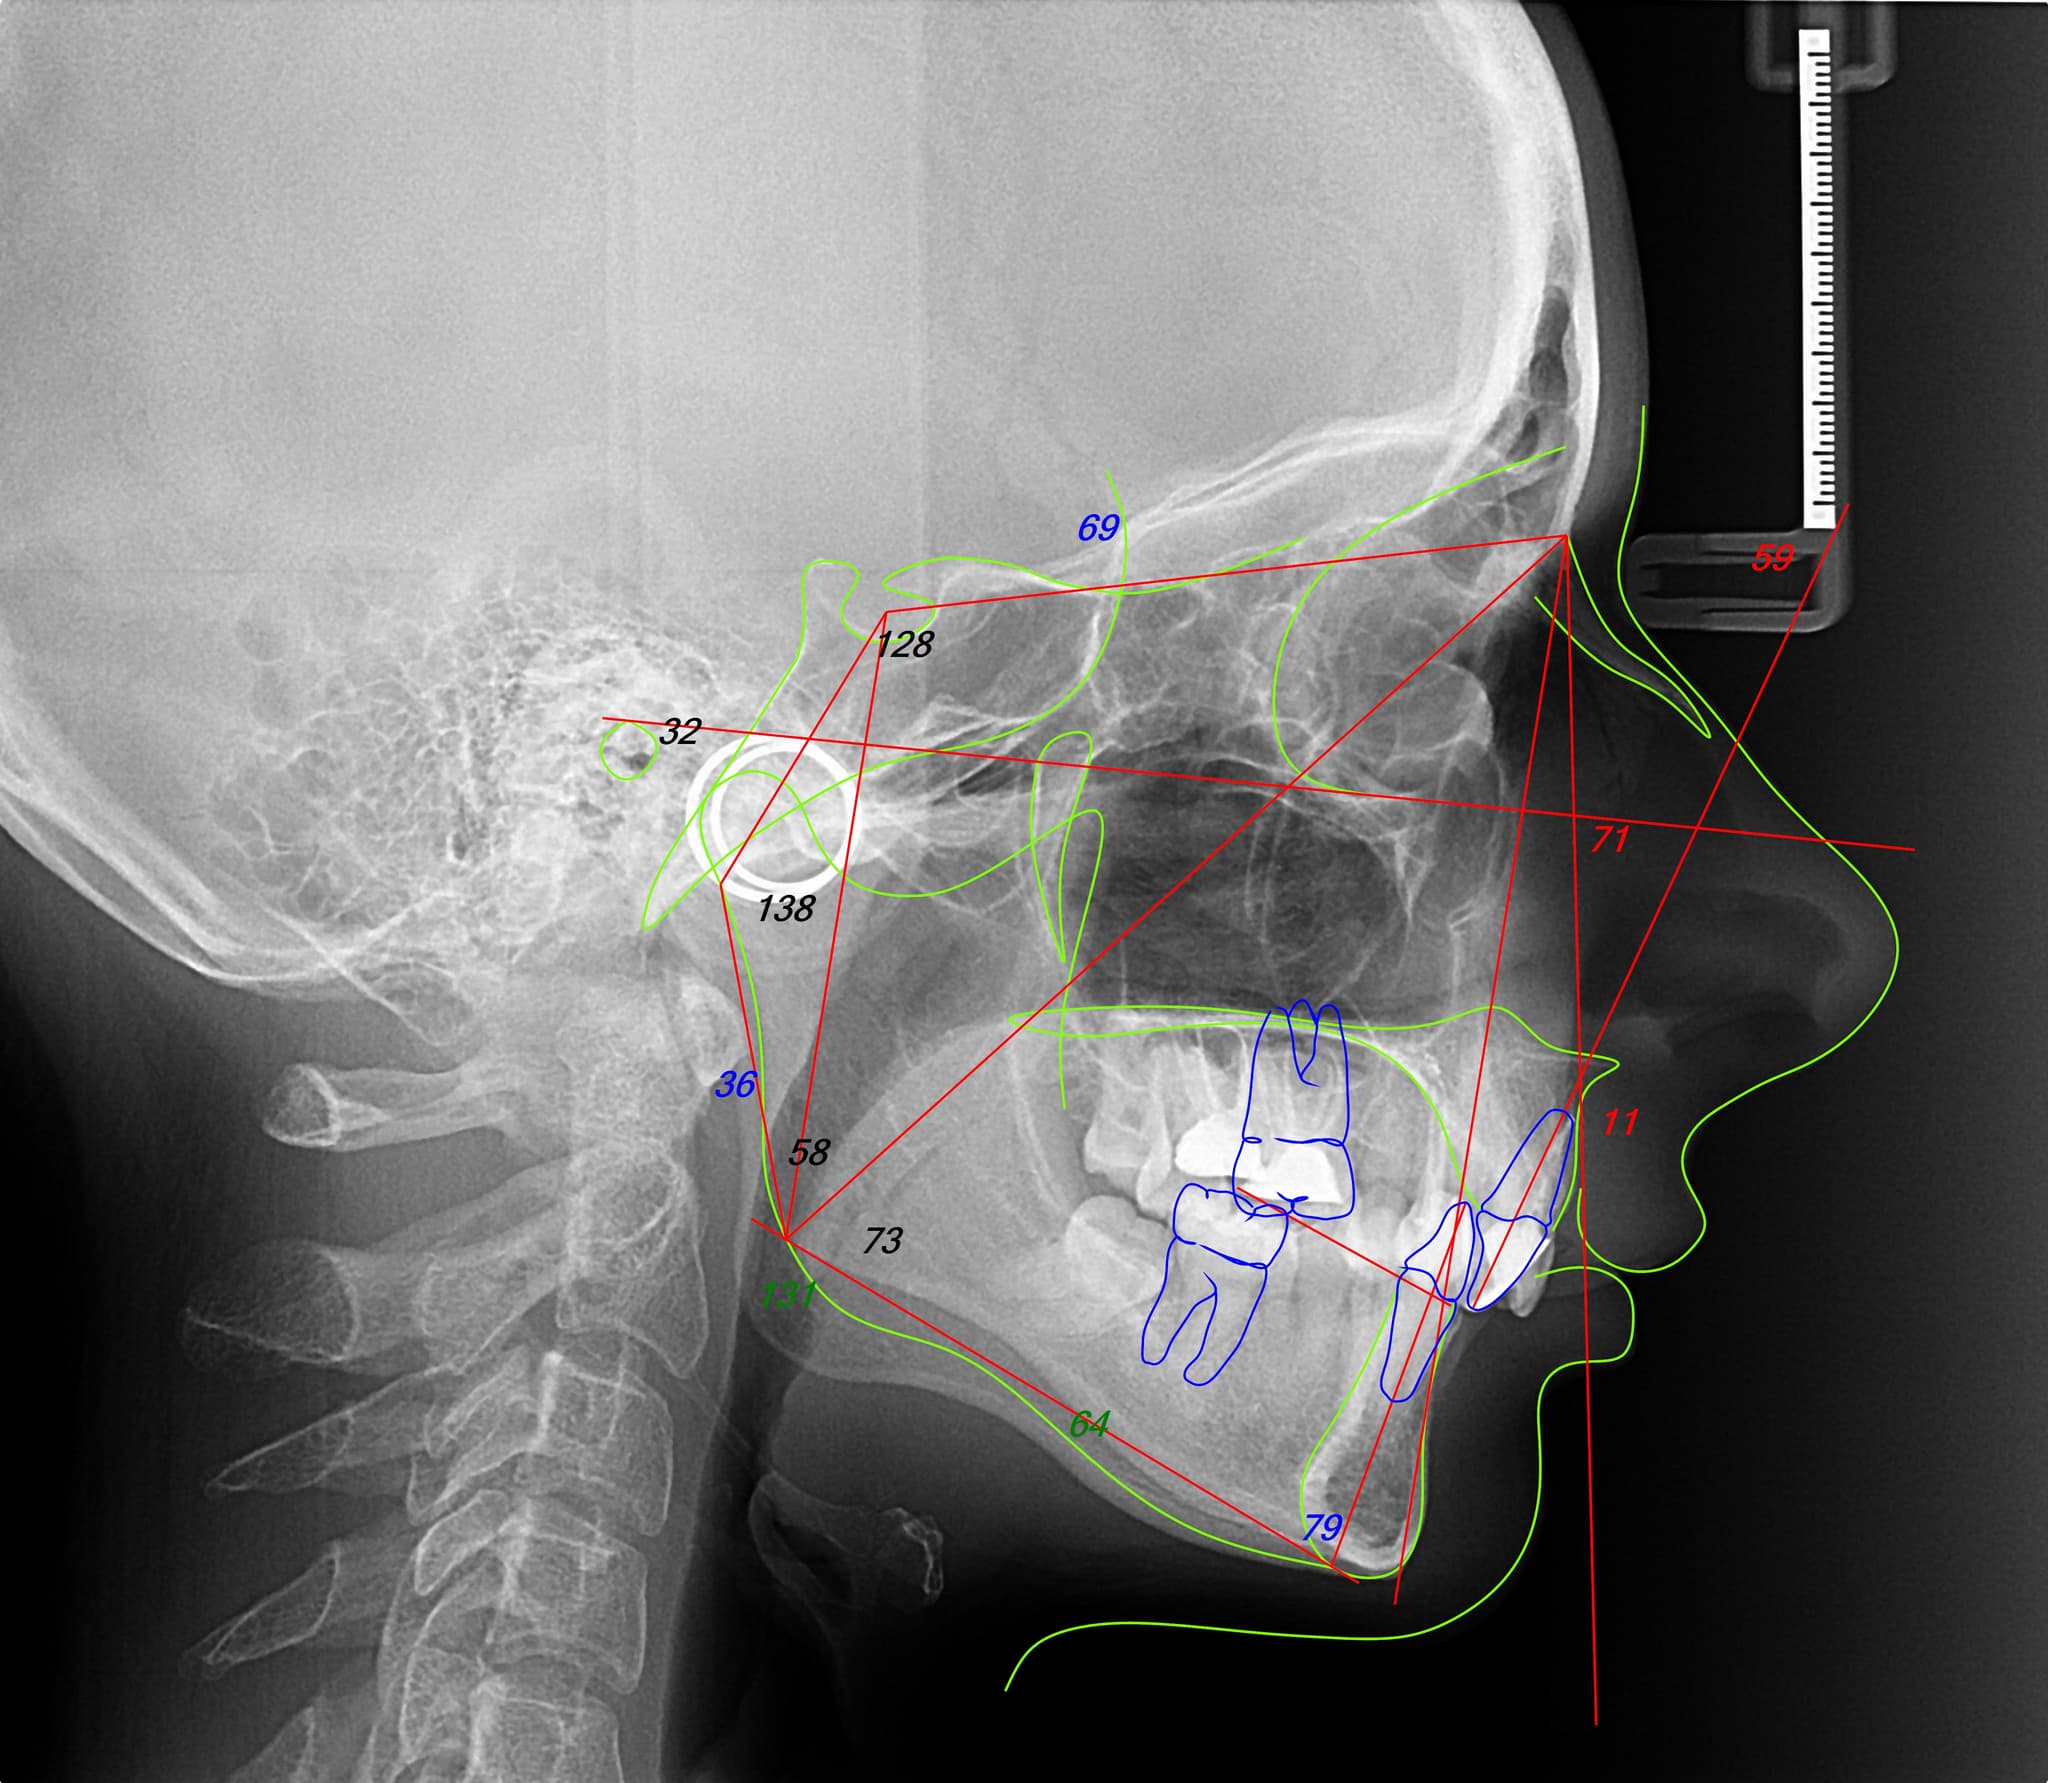

Each orthodontic case begins with a complete digital analysis: facial photos, bite scans, and jaw position. From there, we build a single interdisciplinary plan, aligning orthodontics with the broader treatment goals—be it prosthetic, surgical, or periodontal. This layered but unified approach ensures that every movement serves a long-term, integrated outcome.

Facially driven planning.

We never treat teeth in isolation. Your facial structure, expressions, and muscle dynamics shape the entire orthodontic plan. This allows us to move teeth with intention, aiming for harmony instead of mechanical perfection.